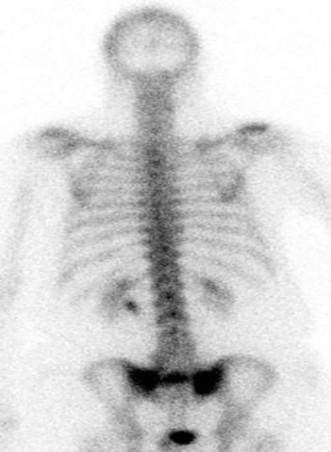

A typical MRI image showing bone marrow edema consistent with a sacral insufficiency fracture. The high signal on STIR sequences highlights the fracture line, often elusive on plain radiographs.